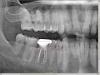

soft Опубликовано 7 февраля, 2010 Автор Поделиться Опубликовано 7 февраля, 2010 И снова здравствуйте.Прокомментируйте, пожалуйста, места на снимке, которые я выделил красной рамкой.Это кариес?Правильно ли я понял, что это находится по десной?Зуб под коронкой разрушается под десной? Ссылка на комментарий

Андрей Опубликовано 7 февраля, 2010 Поделиться Опубликовано 7 февраля, 2010 И снова здравствуйте.Прокомментируйте, пожалуйста, места на снимке, которые я выделил красной рамкой.Это кариес?Правильно ли я понял, что это находится по десной?Зуб под коронкой разрушается под десной?Обзорный снмок дает искажения и артифакты, для уточнения наличия кариеса нужно сделать прицельные снимки. Коронка под подозрением. Ссылка на комментарий

annda Опубликовано 7 февраля, 2010 Поделиться Опубликовано 7 февраля, 2010 (изменено) И снова здравствуйте.Прокомментируйте, пожалуйста, места на снимке, которые я выделил красной рамкой.Это кариес?Правильно ли я понял, что это находится по десной?Зуб под коронкой разрушается под десной?наличие кариеса под большим сомнением.Коронка жуткая,даже учитывая искажение на ОПТГ Изменено 7 февраля, 2010 пользователем annda Ссылка на комментарий

soft Опубликовано 1 марта, 2010 Автор Поделиться Опубликовано 1 марта, 2010 Спасибо большое за ответы. У меня еще вопрос по поводу зуба под коронкой.Я сделал прицельный снимок этого зуба. Насколько я понял, на этом зубе кариес под десной, близко к кости.Что можно сделать с этим?Можно ли снять коронку и вылечить? Ссылка на комментарий